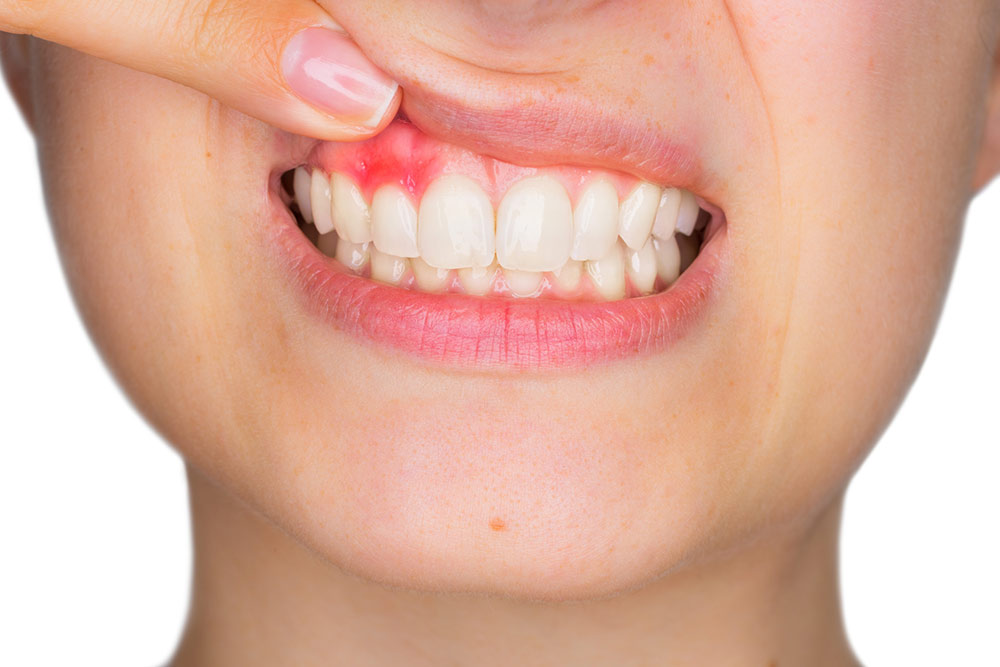

Inflamación / Infección dental

Hinchazón en la cara, encía inflamada o presencia de pus.